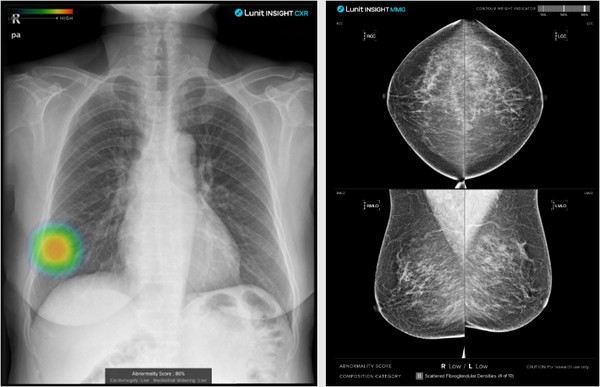

- 주요 사업 부문은 AI 영상 분석 솔루션인 루닛 인사이트(Lunit INSIGHT)와 AI 병리 분석 및 바이오마커 솔루션인 루닛 스코프(Lunit SCOPE)로 나뉜다.

- 루닛 인사이트는 흉부 X선(CXR), 유방촬영술(MMG), 흉부 CT, 유방단층촬영(DBT) 등 의료 영상을 분석해 폐암, 유방암 등 암의 조기 진단을 보조하며, 전 세계 40여 개국 2,000개 이상 의료기관에서 사용된다.